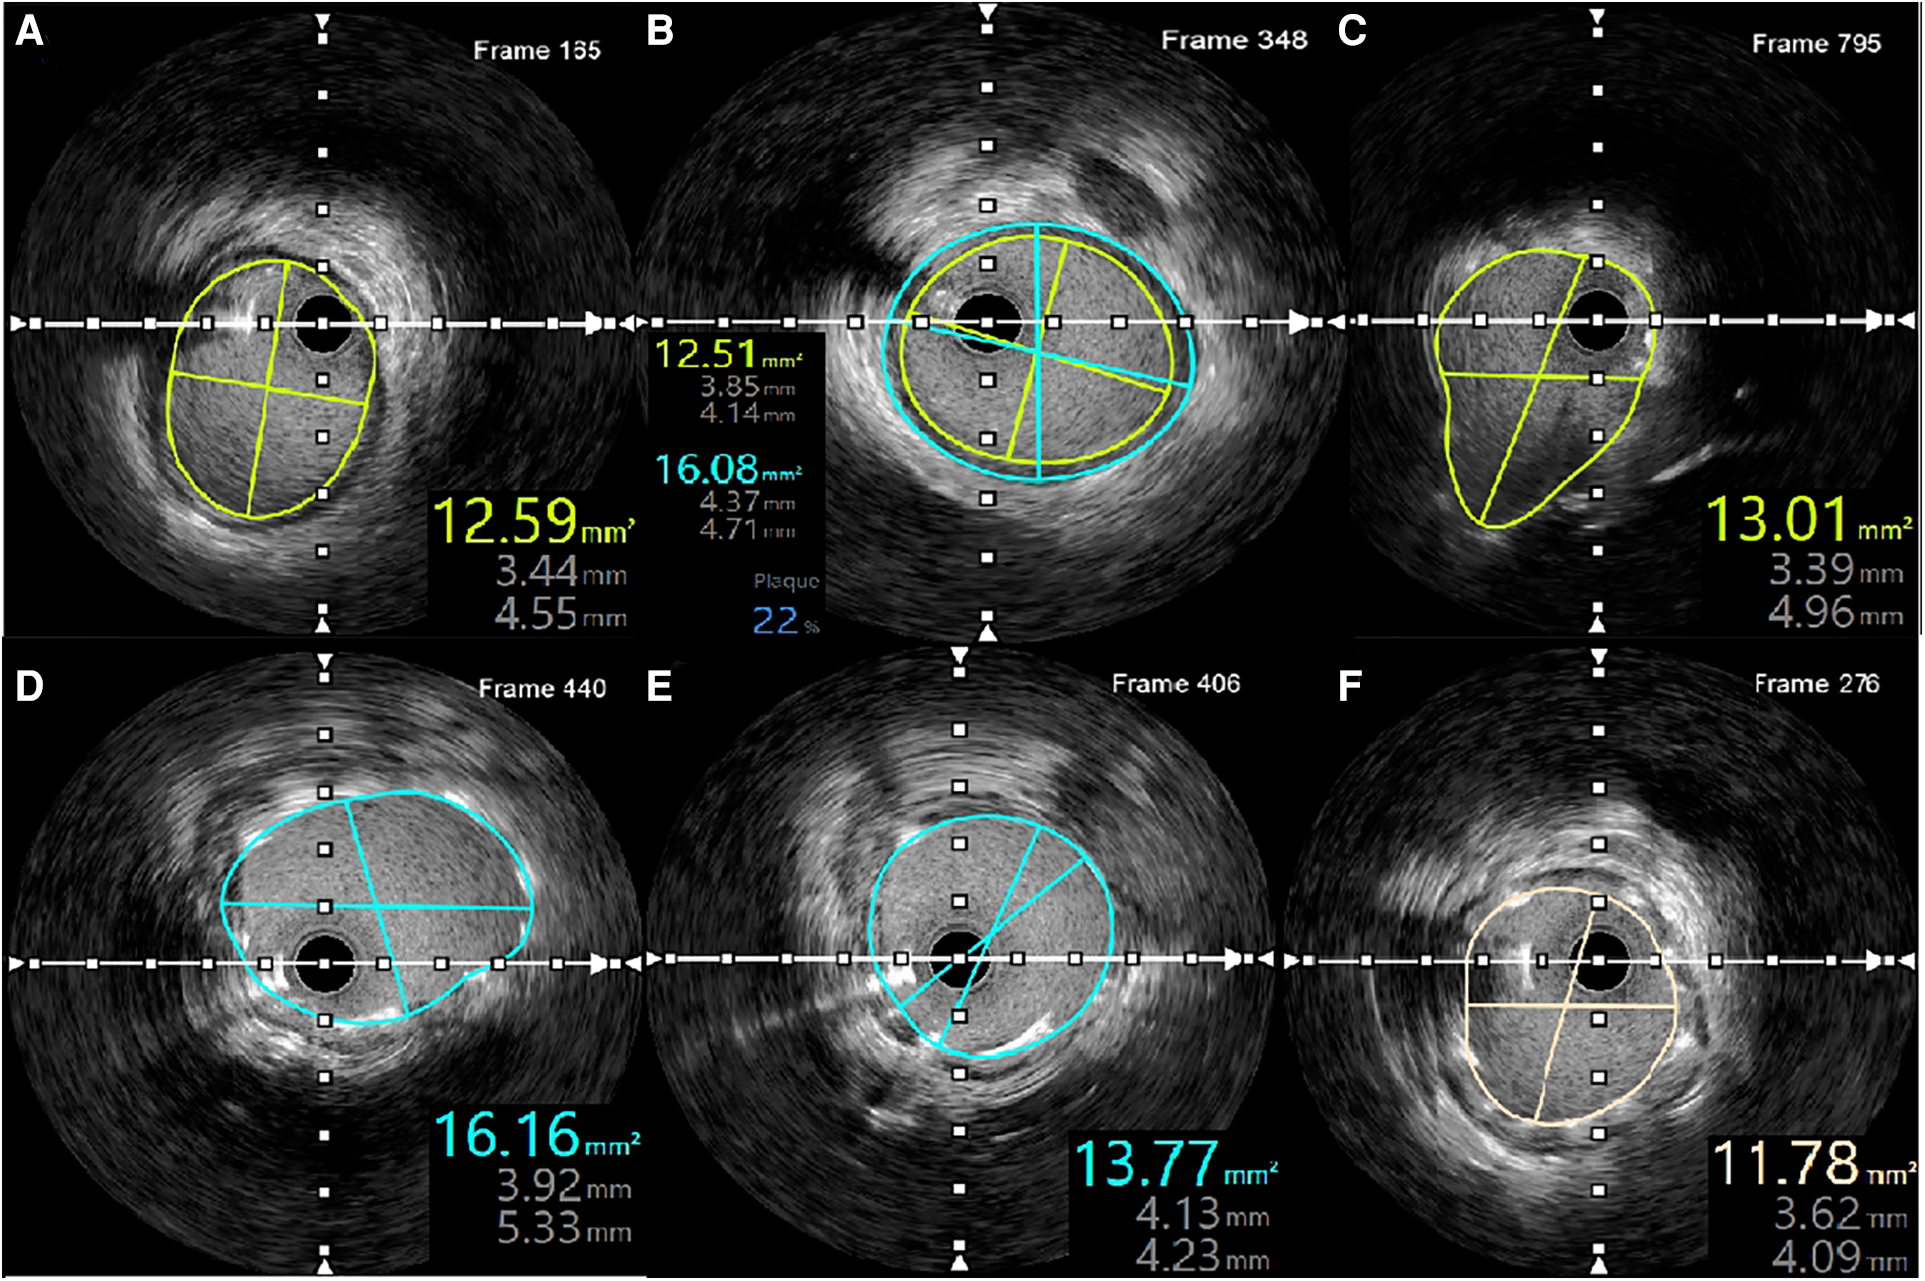

IVUS revealed no evidence of dissection at either the proximal or distal stent edges, as well as the absence of tissue prolapse following PCI. The minimal stent area (MSA) at the distal and proximal ends of the LMCA were measured at 16.16 mm2 and 13.01 mm2, respectively. Meanwhile, the MSA at the LCx ostium was 13.77 mm2. The smallest MSA within the stent was 11.78 mm2, accounting for 94% of the MSA at the distal reference, which was 12.59 mm2. Additionally, IVUS verified adequate stent apposition at both proximal and distal ends (Figure 5).

Figure 5. IVUS measurements following LMCA-LCx PCI. (A) MSA of the distal reference. (B) Plaque burden and distal reference diameter. (C) MSA at the proximal LMCA. (D) MSA at the distal LMCA. (E) MSA at the ostium of the LCx. (F) Smallest MSA within the stent.